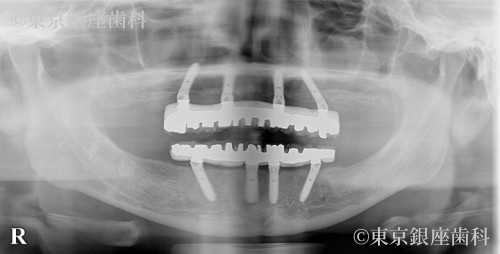

若くして重度歯周病に悩み上下インプラントで改善した40歳代女性の症例

After

施術内容 ワンデイインプラント

長年歯周病に悩み、不安を抱えて来院。上下インプラントで噛み合わせと見た目が改善。術後調整を経て安定し、現在もメンテナンス継続中。

上下ワンデイインプラント